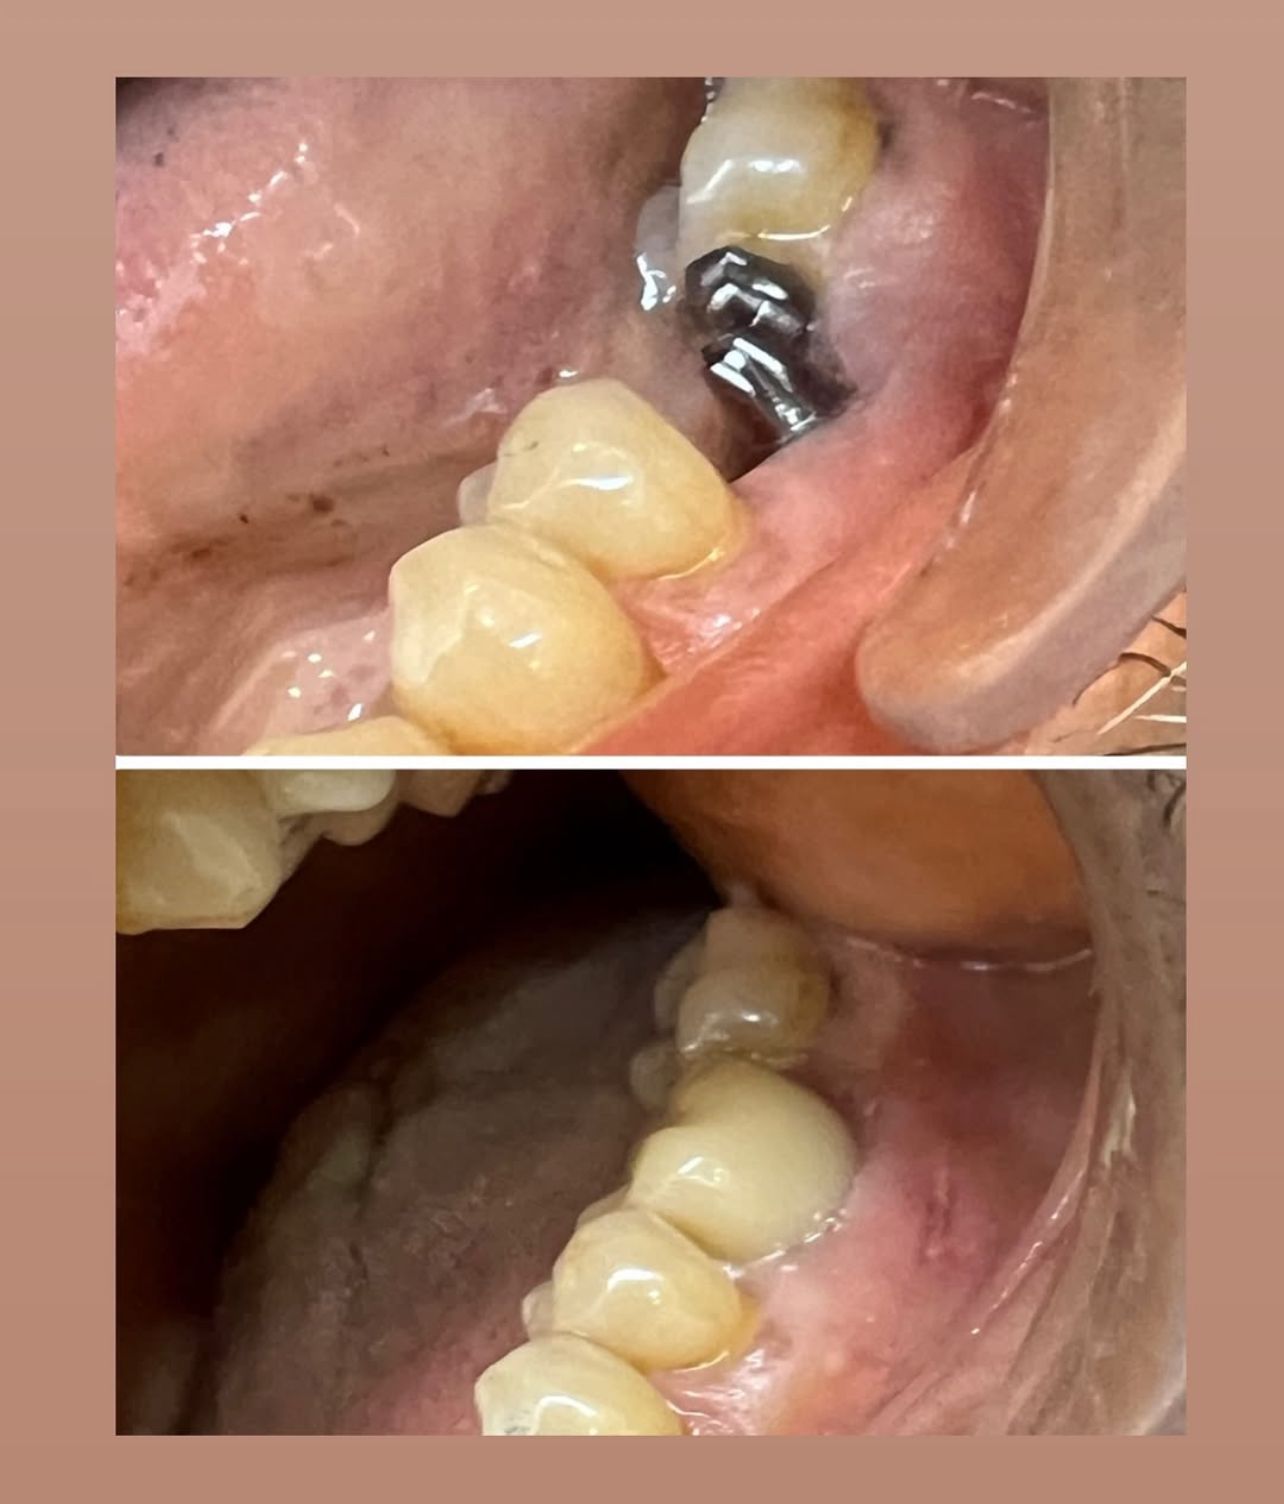

•  DENTAL IMPLANTS